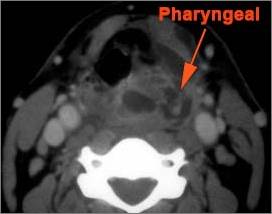

There is excessive enhancement or thickening of the mucosa or hypertrophy of the lymphoid tissue in the nasopharynx.

There is evidence of an abscess within the lymphoid tissue of the nasopharynx.

There is edema within the fat of the adjacent parapharyngeal space.

There is an abscess within the fat of the adjacent parapharyngeal space.